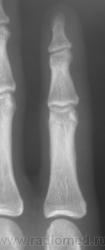

Травма. Пациент направлен на рентгенографию 2 пальца.

Костно-травматических изменений не вижу

Вот это прикол. Настоящая головоломка !!! это инородное тело в области мед края головки осн фаланги 2 пальца.

Ну, не знаю. я тоже ничего не вижу. А тонюсенькая полосочка может быть и артефактом.

Я тоже на это обратил внимание, но посчитал артефактом.

По всей видимости, норму надо писать?

Валентин Львович, вы ж укажите, где локальная болезненность. Может перелом основания осн. фаланги?

??? Головка ср.ф. какая-то скошенная, но деструктивн. изм., повреждений не вижу.

Меня тоже смутила форма головки фаланги.